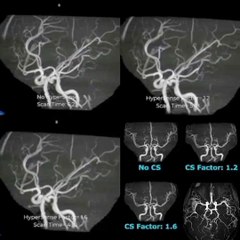

Angiography